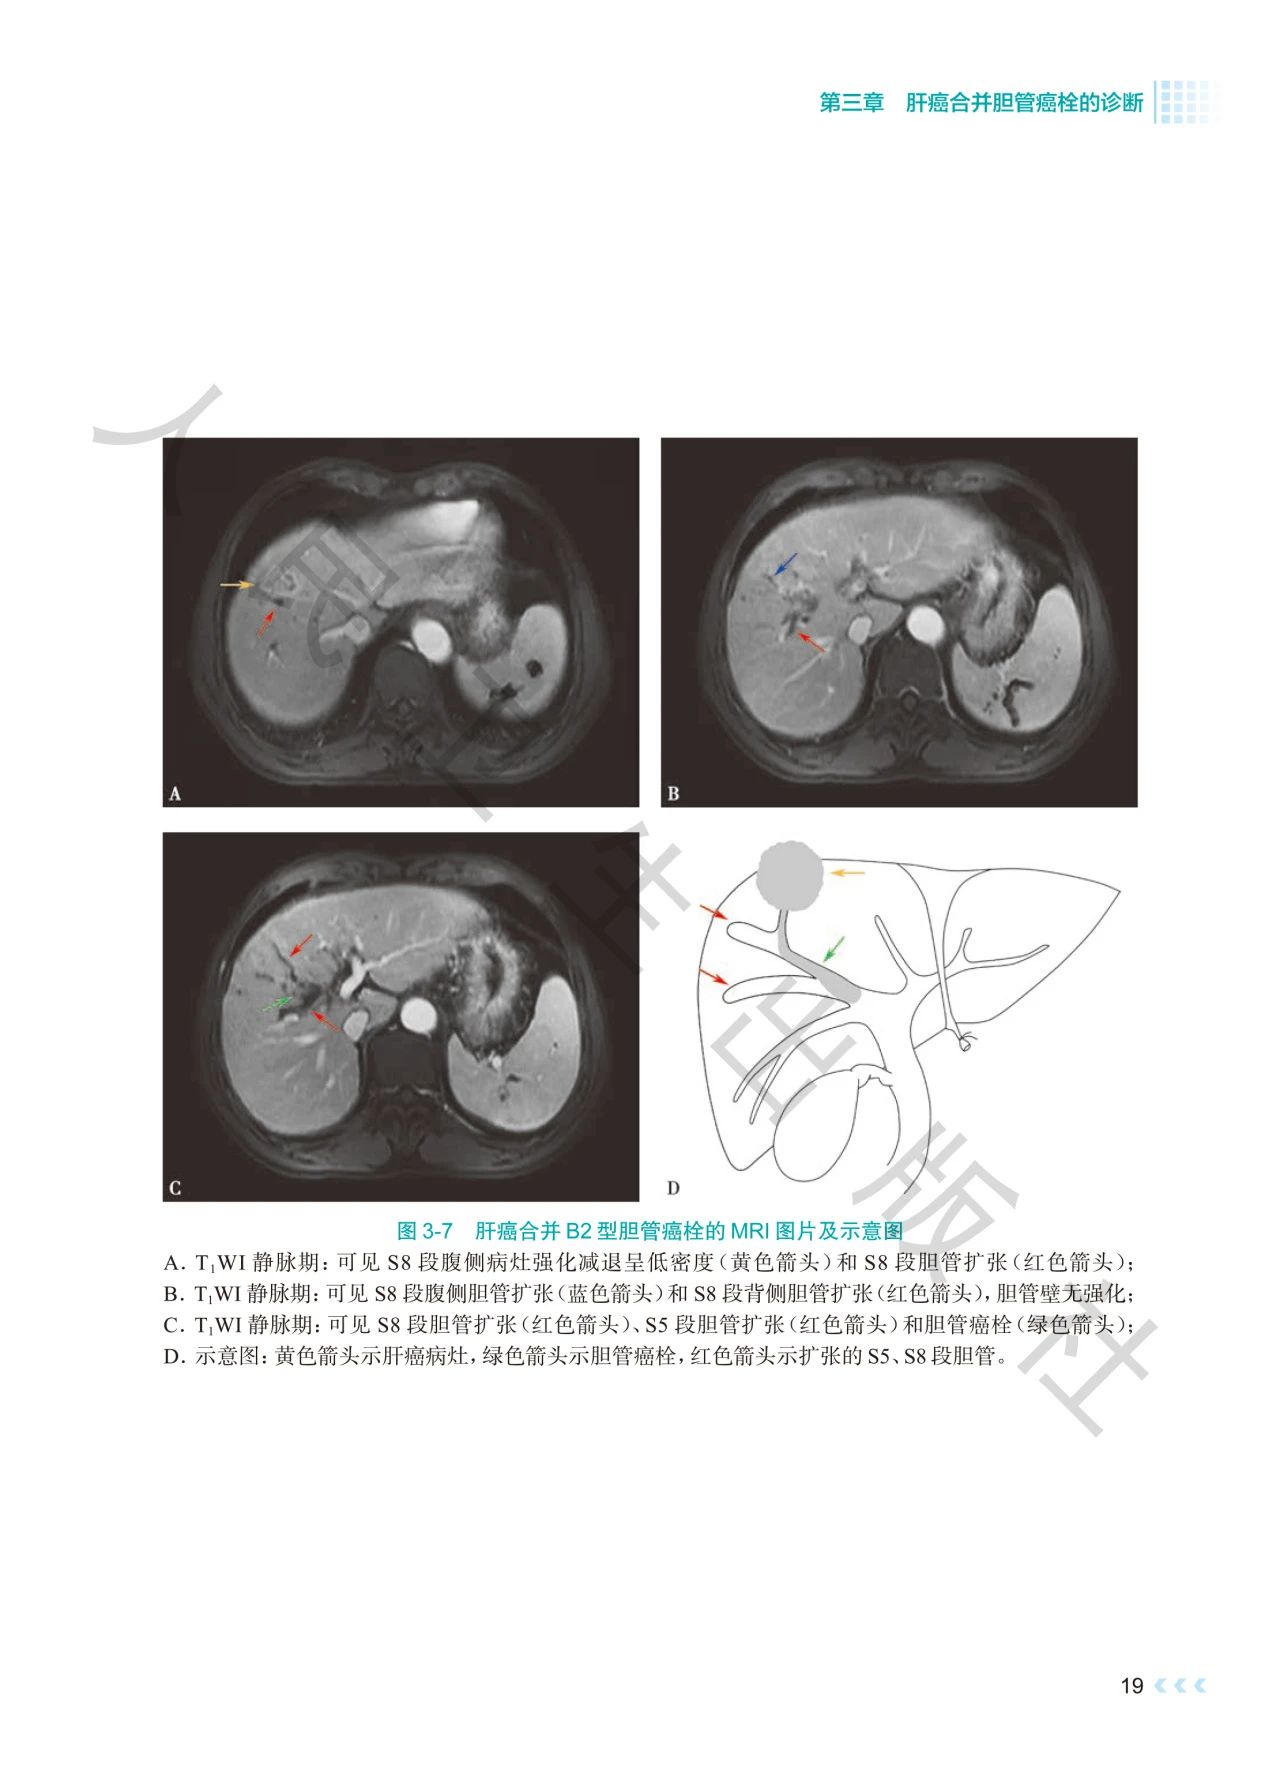

《肝癌合并胆管癌栓诊治》深入探讨了肝癌合并胆管

癌栓诊治领域的焦点问题。书中通过影像图、示意图

、手术图,详细阐述了不同分型胆管癌栓的影像学特

点及手术方式,提出q形胆总管切开取栓方法,强调解

本书通过丰富的示意图、影像图和手术图,对肝癌合

并胆管癌栓的分型、诊断策略、治疗方法等进行了深

入剖析,全面系统地总结了肝癌合并胆管癌栓领域的

前沿理论与临床实践经验。内容科学严谨、实用性强